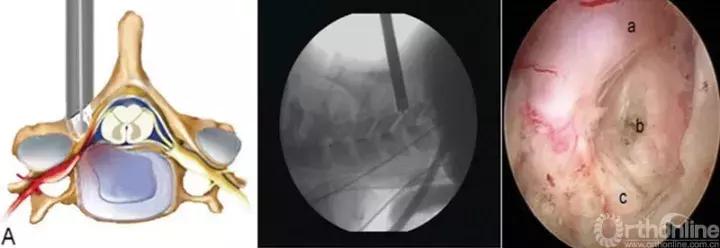

1. 精准穿刺技术:

腰椎间孔入路:正位透视下,穿刺针应该“正位朝尖,髂嵴靠边,侧位循突,针指后缘。”也就是说,正位上穿刺针朝向上关节突尖部,穿刺轨迹离髂嵴有一定距离,以便操作时工作通道可以向头侧或尾侧倾斜,侧位上沿着上关节突进入到硬膜外腔,针的末端不超过椎体后缘(正位上已达到椎弓根内缘),穿刺针水平面倾角根据不同节段和椎间孔的大小酌情调整。

腰椎板间入路:与椎间孔入路相比,椎板间入路穿刺要求较为简单。然而,在初期开展节段,如穿刺定位不准,亦会造成手术延误,甚至手术失败。理想的穿刺位置应该是位于椎板窗中央与下关节突之间,以便操作时可以向外侧和内侧调整。通道偏外,术中显露困难且容易过多切除关节突,偏内的位置会造成处理侧隐窝不足。

椎间孔入路操作技巧应注意“关突引导,循骨而进,成型忌粗,遇痛即止。”也就是说,以上关节突为引导,沿着上关节突进入到硬膜外间隙,固定通道后,探及底面为硬性骨组织后,用环锯进行一次成型,成型后半过程如患者出现神经疼痛,应停止前进,术中并用透视证实成型工具末端不超过椎弓根内侧缘。